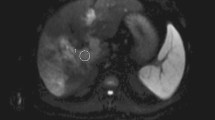

In recent studies, contrast-enhanced ultrasound appeared superior to both colour-Doppler ultrasound and spiral CT for the detection and characterisation of PVT [10, 13]. The main advantages of contrast-enhanced ultrasound (CEUS) over other modalities are that it is performed in real time and it has the ability to detect a small thrombus even in peripheral portal branches. However, the technique is observer-dependent and sometimes hampered by the presence of bowel gas [14]. Magnetic resonance imaging is of great value in the assessment of PVT [15, 16]. Recent reports have highlighted the potential of diffusion-weighted imaging to differentiate benign from malignant PV thrombus. However, MR is somewhat restricted by spatial resolution as well as lack of availability in some centres. A typical MR protocol with a slice thickness and interval of 5 mm/5 mm could potentially mask a small thrombus and might also be a source of error due to partial volume effects.